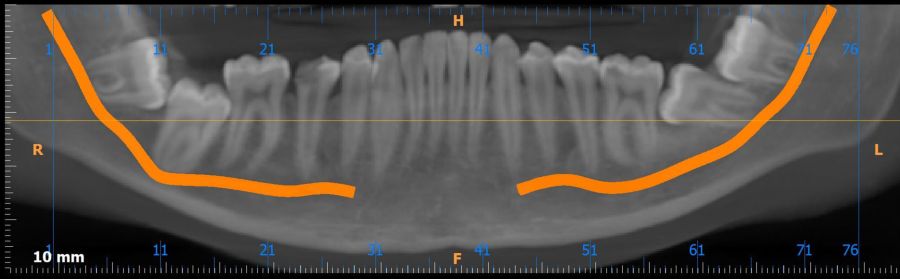

Métodos: Se presenta el caso clínico de un paciente varón de 18 años en el que, tras la realización de una CBCT de la arcada mandibular, se observó la retención de los segundos molares mandibulares permanentes junto con los terceros molares mandibulares.

Resultados: Dada la ausencia de signos radiológicos, el paciente optó por una actitud expectante, pendiente de revisiones posteriores que pudieran indicar cambios y en consecuencia plantear una actitud intervencionista.

Methods: We present the case of an 18-year-old male patient in whom, after performing a CBCT of the mandibular arch, retention of the permanent mandibular second molars was observed, along with the mandibular third molars.

Results: In the absence of radiological signs, the patient opted for an expectant approach, with follow-up evaluations to detect any changes that might warrant an interventional strategy.